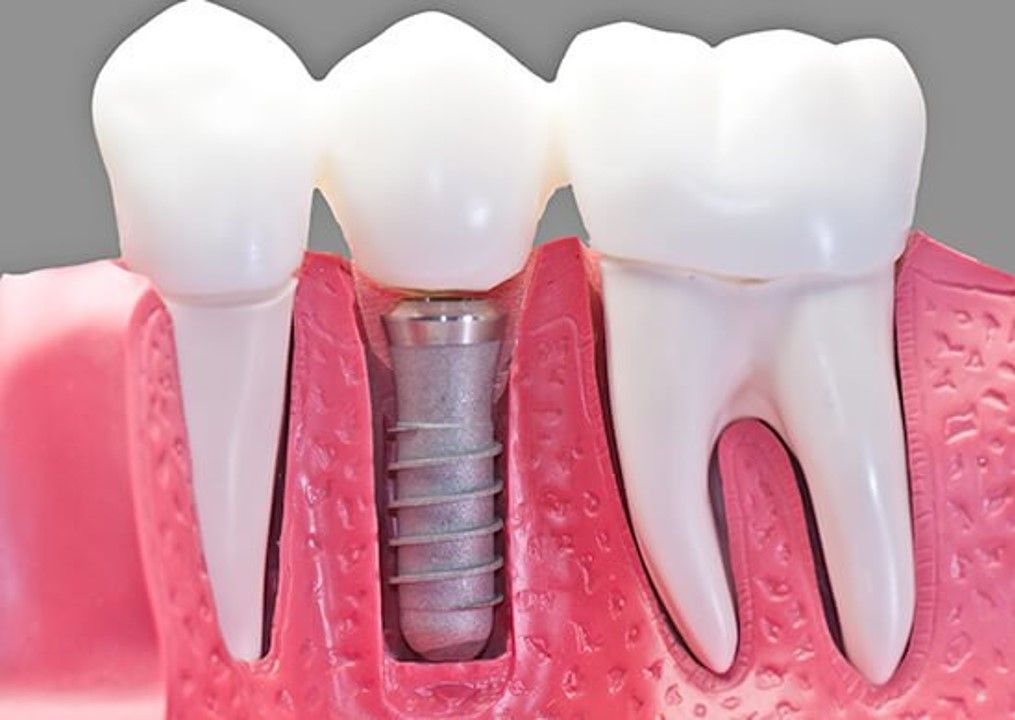

- Implantes dentales